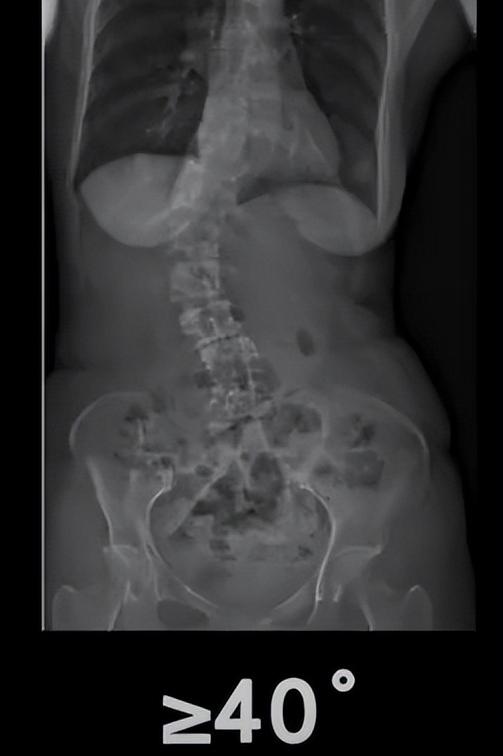

二、如何判断脊柱侧弯的严重程度?

X光显示0°-10°,10°-20°为轻微侧弯,一般25°一下相对就比较轻微,20°-40°是重度侧弯,40°以上就相对严重。

发现侧弯时建议到医院观察是否有恶化风险,是否需要治疗可能会引起恶化的风险,由医生判断是否需要治疗。